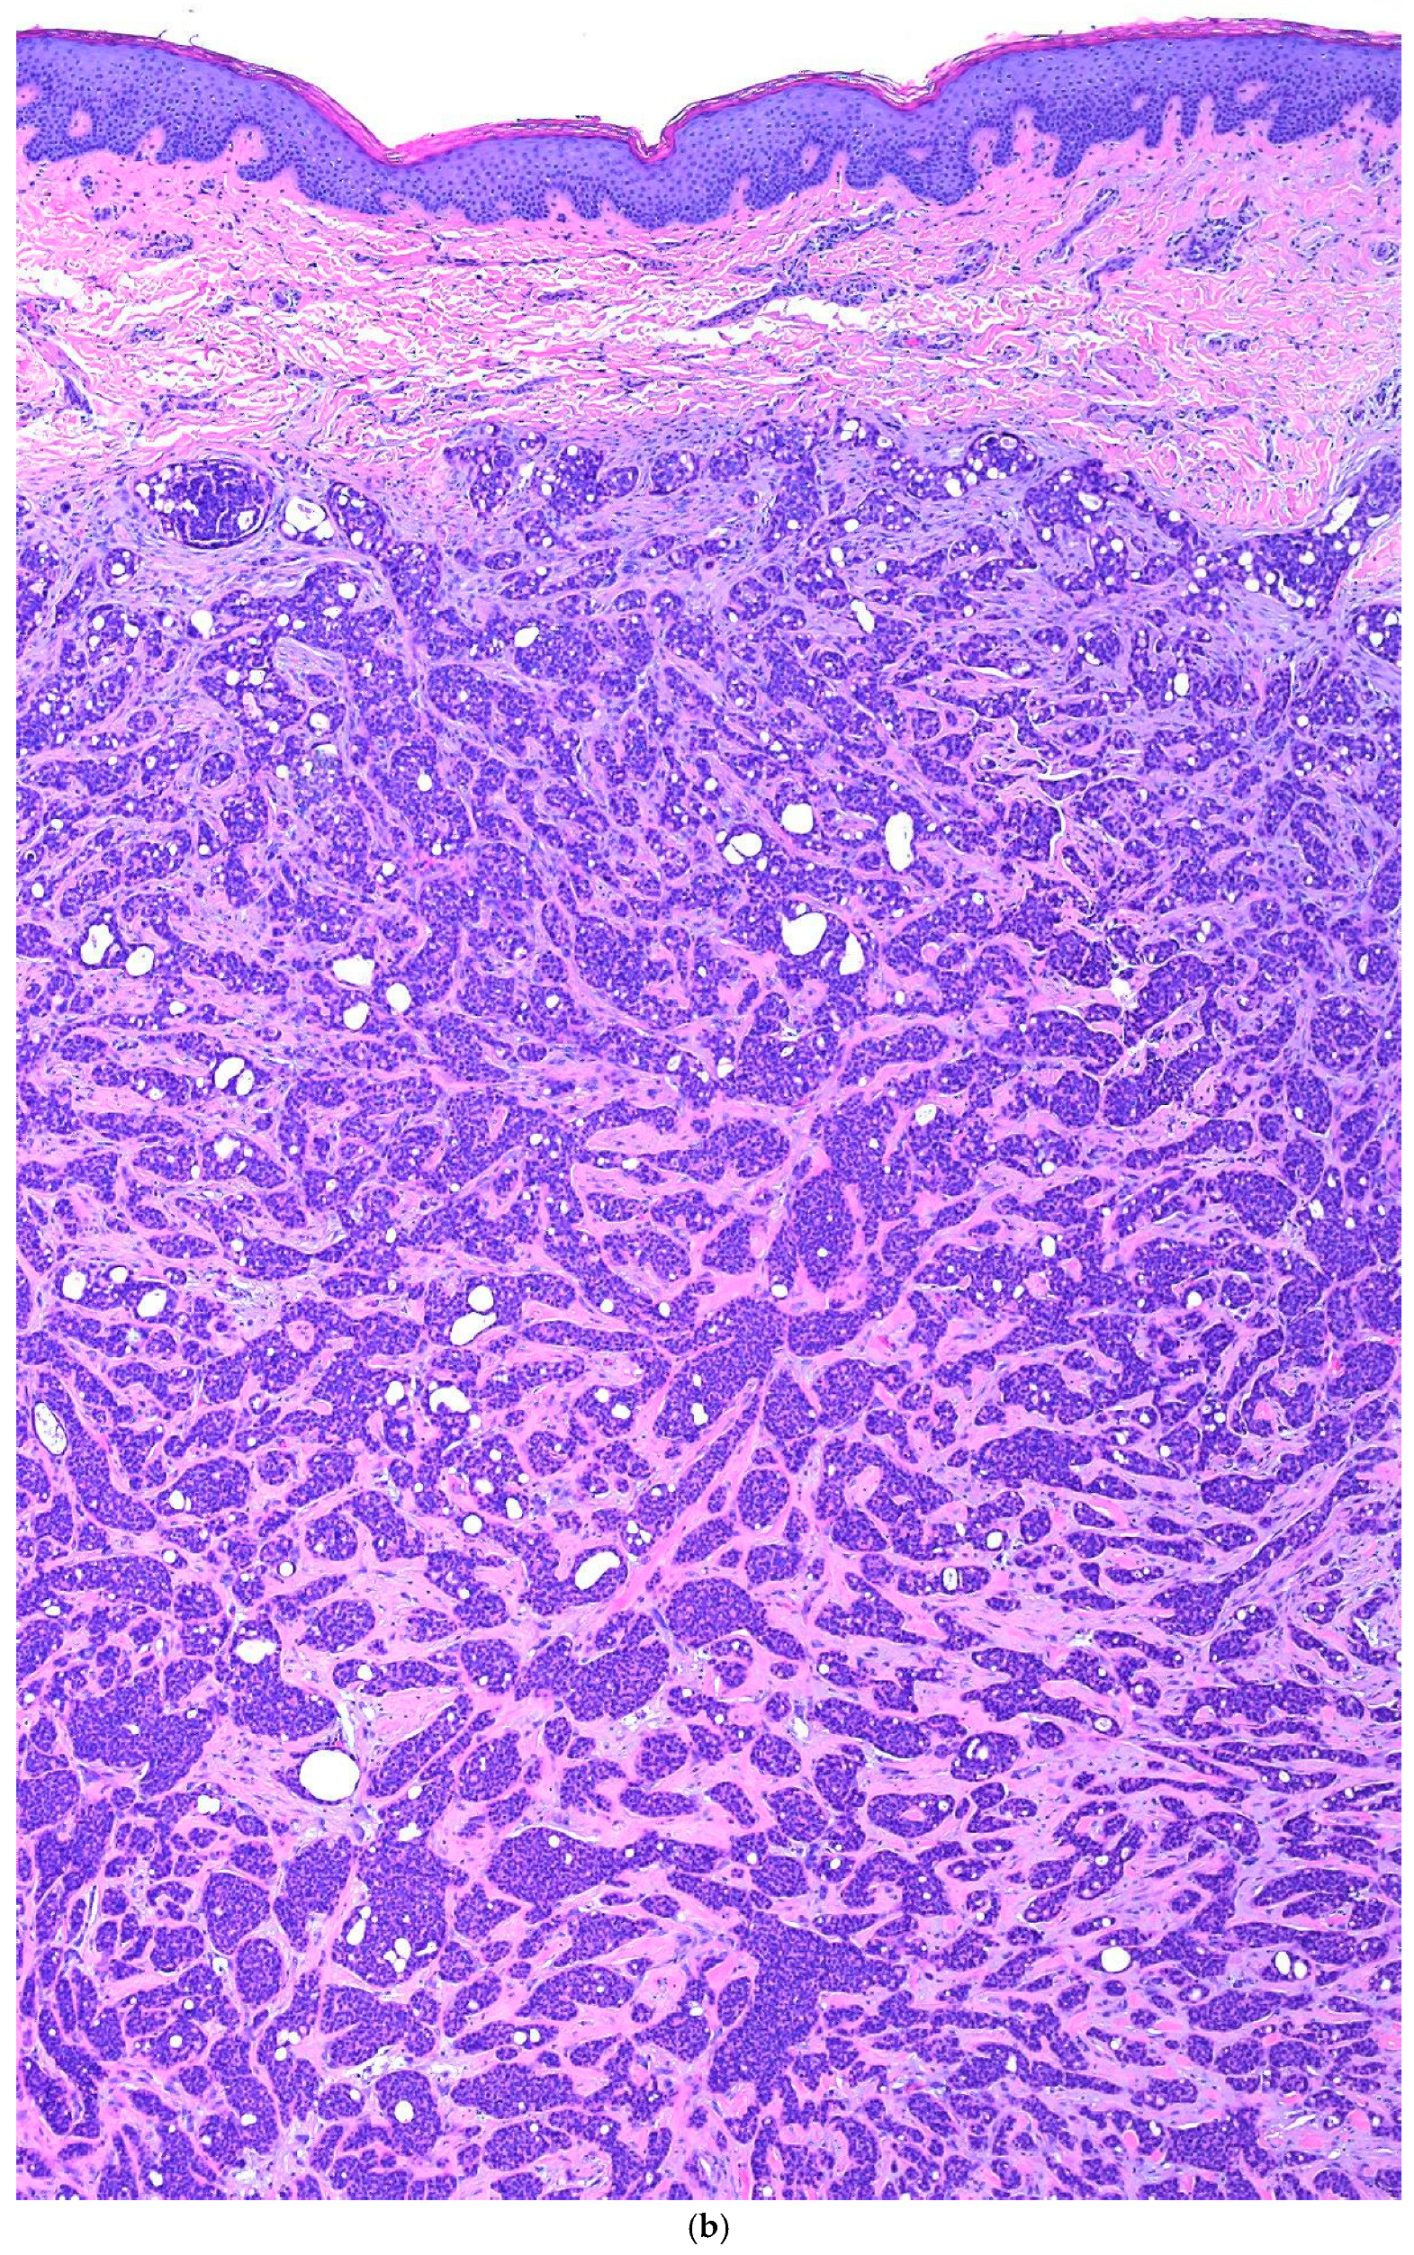

Primary Cutaneous Cribriform Apocrine Carcinoma: A Case Report and Narrative Review

3. Case